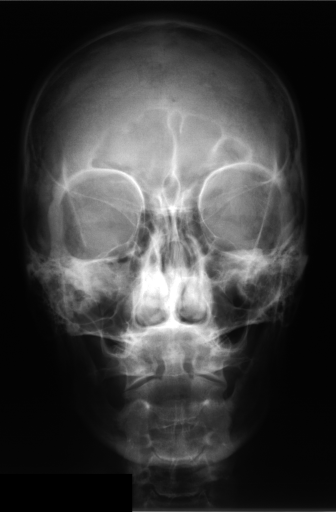

Details of the IRMA database is described in literature [24],[27],[25]. IRMA dataset offers 12,677 images for training and 1,733 images for testing. Figure 4 shows some sample images from the dataset long with their IRMA code in the format TTTT-DDD-AAA-BBB.